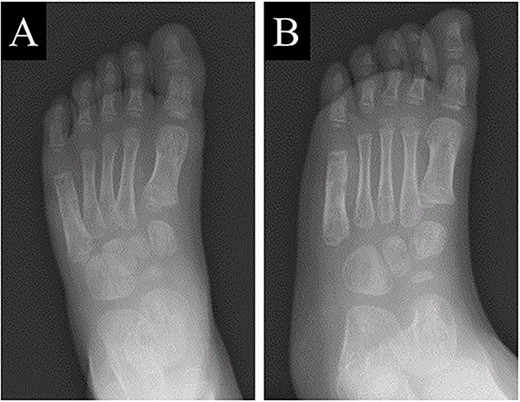

A 21-month-old Japanese female infant presented with a swollen mass on the dorsolateral aspect of the left foot. Her parents noticed the mass and brought the patient to our hospital. The patient had no past medical histories or complications prior to the occurrence. In addition, she received the BCG vaccine at the age of 4 months in Japan. At first visit to our hospital, physical examination revealed the ~3 × 3 cm mass was located on the dorsolateral aspect of the left foot and was hard accompanied by local heat (Fig. 1). Plain radiographs of the left foot showed a lytic lesion without periosteal reaction in the fifth metatarsal bone (Fig. 2). Magnetic resonance imaging (MRI) showed an isointense lesion on T1-weighted images and a hyperintense lesion on T2-weighted images around and within fifth metatarsal (Fig. 3). Gallium scintigraphy revealed intense uptake in the patient’s left foot (Fig. 4). In addition, laboratory examination was within normal. Based on medical history, clinical and imaging findings, we considered the possibility of neoplasia or osteomyelitis and performed an open debridement and biopsy of the lesion to make a diagnosis. The lesion was yellow and consisted of weak, adipose-like tissue that surrounded and continued into the inferior of the fifth metatarsal bone (Fig. 5). The lesion inside and outside the bone was resected as much as possible. Histopathologic examination of the lesion showed granulomatous inflammation including anaplastic giant cells, Langerhans-type giant cells and caseous necrosis (Fig. 6). Based on these results, TB or BCG osteomyelitis was considered as a diagnosis. The tuberculin test was positive, but the QuantiFERON TB test was negative. In addition, samples analyzed using polymerase chain reaction did not identify M. tuberculosis, but did identify the BCG Tokyo-172 strain. Per these findings, the patient was diagnosed with BCG osteomyelitis of the fifth metatarsal and oral treatment with anti-TB medicine including isoniazid (100 mg/day) and rifampicin (150 mg/day) was started. Clinical findings included reduction in swelling of the mass and gradual remodeling of the lytic lesion of the fifth metatarsal on plain radiographs (Fig. 7). However, 10 months after starting the anti-TB treatment, the mass recurred, and MRI revealed a residual high-intensity lesion around and inside the fifth metatarsal on T2-weighted fat-suppressed images (Fig. 8). It was determined that the lesion was difficult to control with anti-TB treatment alone, so an open debridement for the lesion was performed again. Histopathologic examination of the lesion revealed an epithelioid granuloma with necrosis. Therefore, the anti-TB treatment was continued. Six months after the second surgery, clinical and radiographic image findings showed complete improvement (Fig. 9). As a result, anti-TB treatment was ended. At the time of writing this report, 8 years after starting anti-TB treatment, there has been no recurrence.

Plain radiographs of the left foot showing a lytic lesion without periosteal reaction in the fifth metatarsal bone in (A) anteroposterior and (B) oblique views.